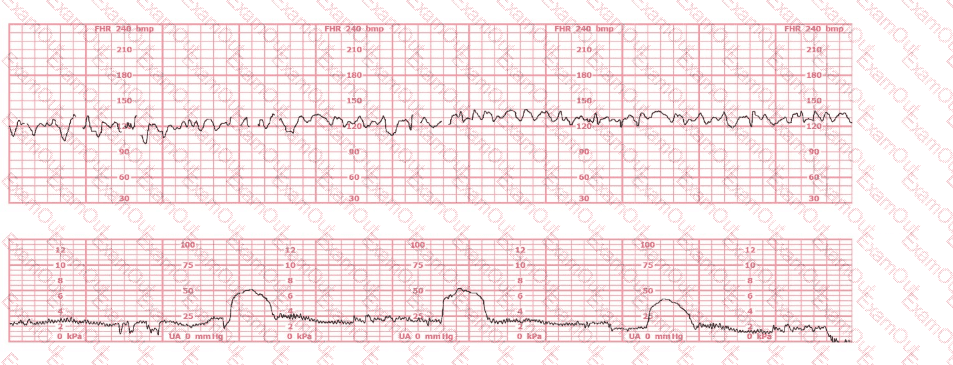

Based on the fetal heart rate tracing shown, the expected fetal pH would be: